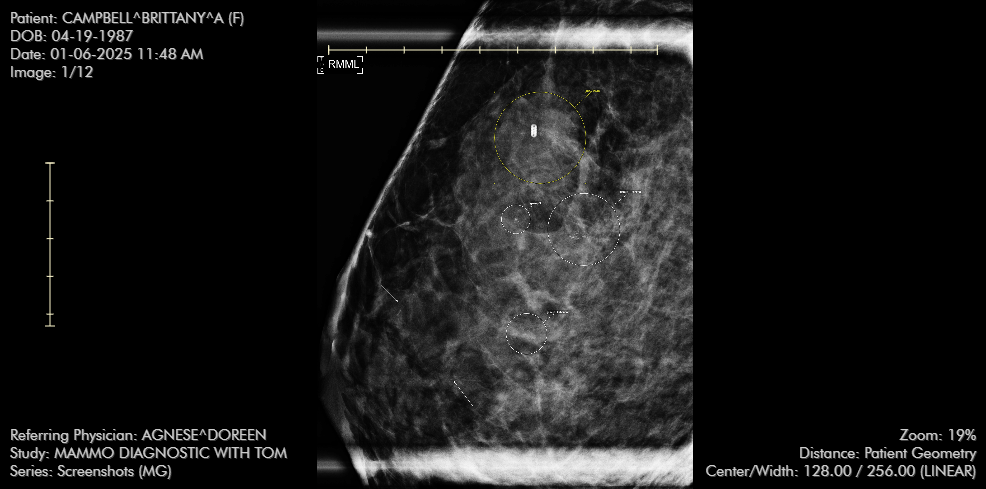

I am pregnant and have breast cancer

Having breast cancer while being pregnant has been one of my life’s greatest challenges so far. It has been extremely overwhelming to say the least. On top of receiving chemo treatments, undergoing surgeries and attending appointments, I also am parenting a wild toddler, maintaining and caring for my marriage, and keeping two dogs alive.